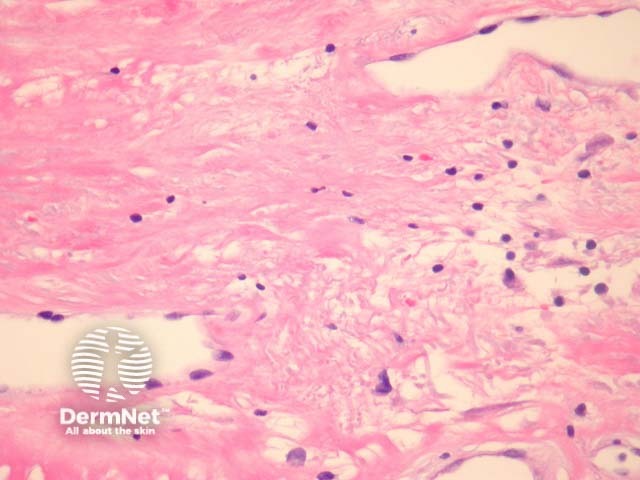

Chronic radiation dermatitis shows dermal sclerosis, elastosis and vascular ectasia overlying an epidermis which is often hyperkeratotic (figure 1). There may be epidermal spongiosis or impressive basal vacuolar change (figure 2). The dermal vessels are typically quite dilated in later stages (figure 3). Both the stroma fibroblasts and endothelial cells may show some hyperchromasia, enlargement and atypia (radiation fibroblasts, figure 3). There is often a mixed inflammatory response.

Figure 3